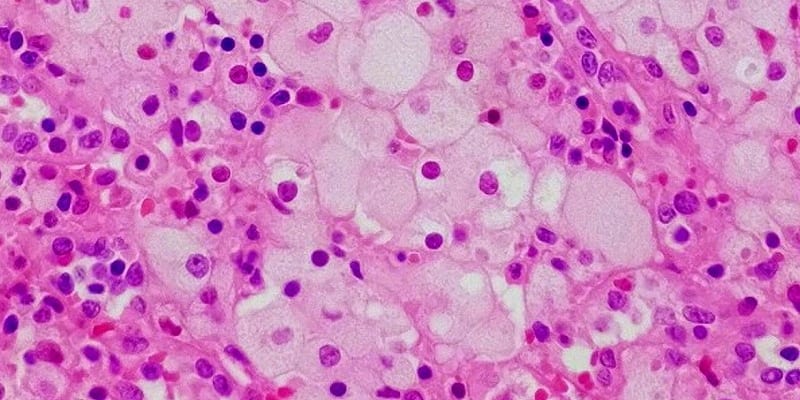

Болезнь Нимана-Пика Тип А: Симптомы и лечение

Раздел: Визуальный дайджест